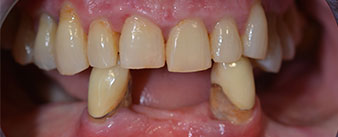

The 64-year-old patient presented with residual dentition of teeth 38, 33 and 43 and a clasp denture in the mandible (Fig. 1 and 2).

residual dentition

Fig. 1

Fig. 2